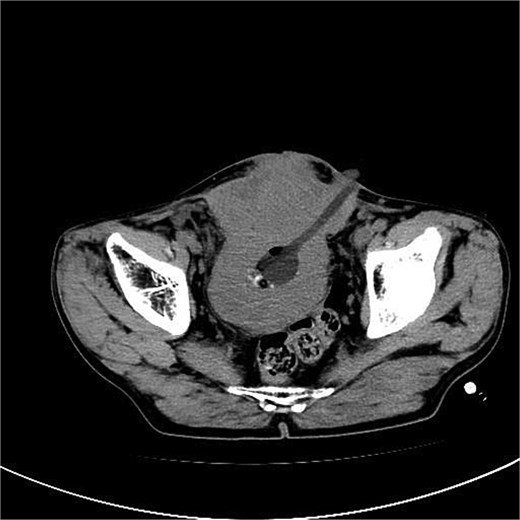

A 53-year-old male, presented to a local hospital in April 2021 due to lower back discomfort. There was no weight loss, fatigue, fever, or other systemic symptoms. Urinalysis showed leukocytes (+++); computed tomography (CT) revealed a 76 × 74 mm stone, bladder wall thickening, and dilation of the bilateral renal pelvis and ureters (Fig. 1). Subsequently, he underwent pubic bladder incision for stone removal and bladder diversion at that hospital. Postoperatively, the incision site was swollen, exuding fluid, and did not heal over an extended period. A total of 14 months after the initial surgery, he was admitted to our hospital. On examination, there was excessive granulation tissue proliferation around the bladder incision wound and near the bladder diversion tube, with surface exudation and easy bleeding upon touch (Fig. 2). Upon admission, urinalysis showed leukocytes (++), occult blood (++), glucose (++), and protein (++). Postprandial blood glucose level was 19.58 mmol/l. Urine culture indicated tropical pseudo-filamentous yeast and Enterococcus. Secretion culture showed E. coli and Klebsiella pneumoniae subsp. Blood routine test indicated white blood cell count and highly sensitive C-reactive protein within normal ranges. He received infection control, glucose management, and wound care, but the wound did not heal. Abdominal CT and pelvic magnetic resonance imaging (MRI) revealed bladder wall thickening and soft tissue in the anterior pelvic area (Fig. 3). Histopathological results from abdominal wall tissue biopsy indicated moderately differentiated squamous cell carcinoma. Immunohistochemistry indicated: CK(pan)(+), CK20(−), CK7(−), PAX-8(−), GATA3(−), P63(+), P53(+), Ki-67(+) at 40% (Fig. 4).

Abdominal CT showed a massive bladder stone measuring 76 × 74 mm, thickened bladder walls.